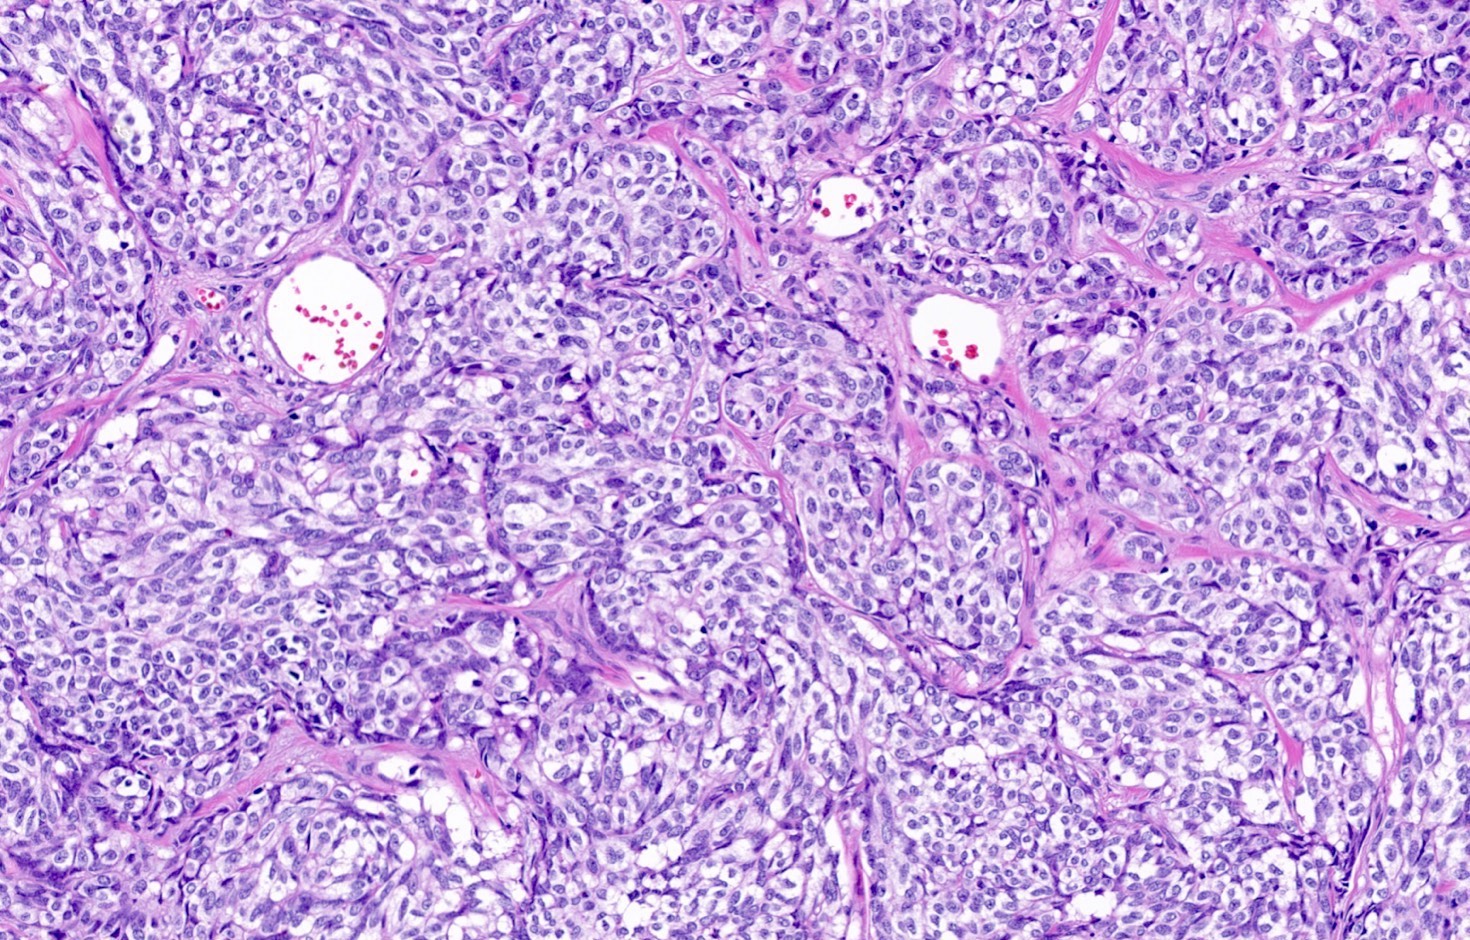

Microscopic (histologic) description

- Diagnostic criteria

- Neuroendocrine tumor with size ≥ 5 mm with < 2 mitoses/2 mm2 and absence of necrosis

- Neuroendocrine growth pattern (organoid, trabecular, rosette formation, nested) or pseudoglandular, follicular and papillary growth

- Tumor cells are uniform with a polygonal shape, round to oval nuclei with salt and pepper chromatin as well as inconspicuous nucleoli and moderate to abundant eosinophilic cytoplasm

- Spindle cells and clear cell features can be seen

- Stroma is fine and highly vascularized; hyalinization, cartilage or bone formation are possible

- Reference: Curr Oncol 2018;25:S86

Microscopic (histologic) images

Contributed by Philippe Joubert, M.D., Ph.D., Jijgee Munkhdelger, M.D., Ph.D. and Andrey Bychkov, M.D., Ph.D.

A 55 year old woman had a lower left lobectomy showing a well circumscribed flesh colored tumor. Histologic details are shown in the image above. Regarding this entity, which of the following statements is true?

A. CDX2 is usually negative in the lung and is useful to differentiate from a metastasis of an intestinal origin. The image shows a tumor with a trabecular pattern and pseudorosettes. The stroma is highly vascularized. Tumor cells are monotonous with scant to moderate eosinophilic cytoplasm. Nuclei are round to oval with salt and pepper chromatin and inconspicuous nucleoli. No mitoses are seen. These features are consistent with a typical carcinoid lung tumor.